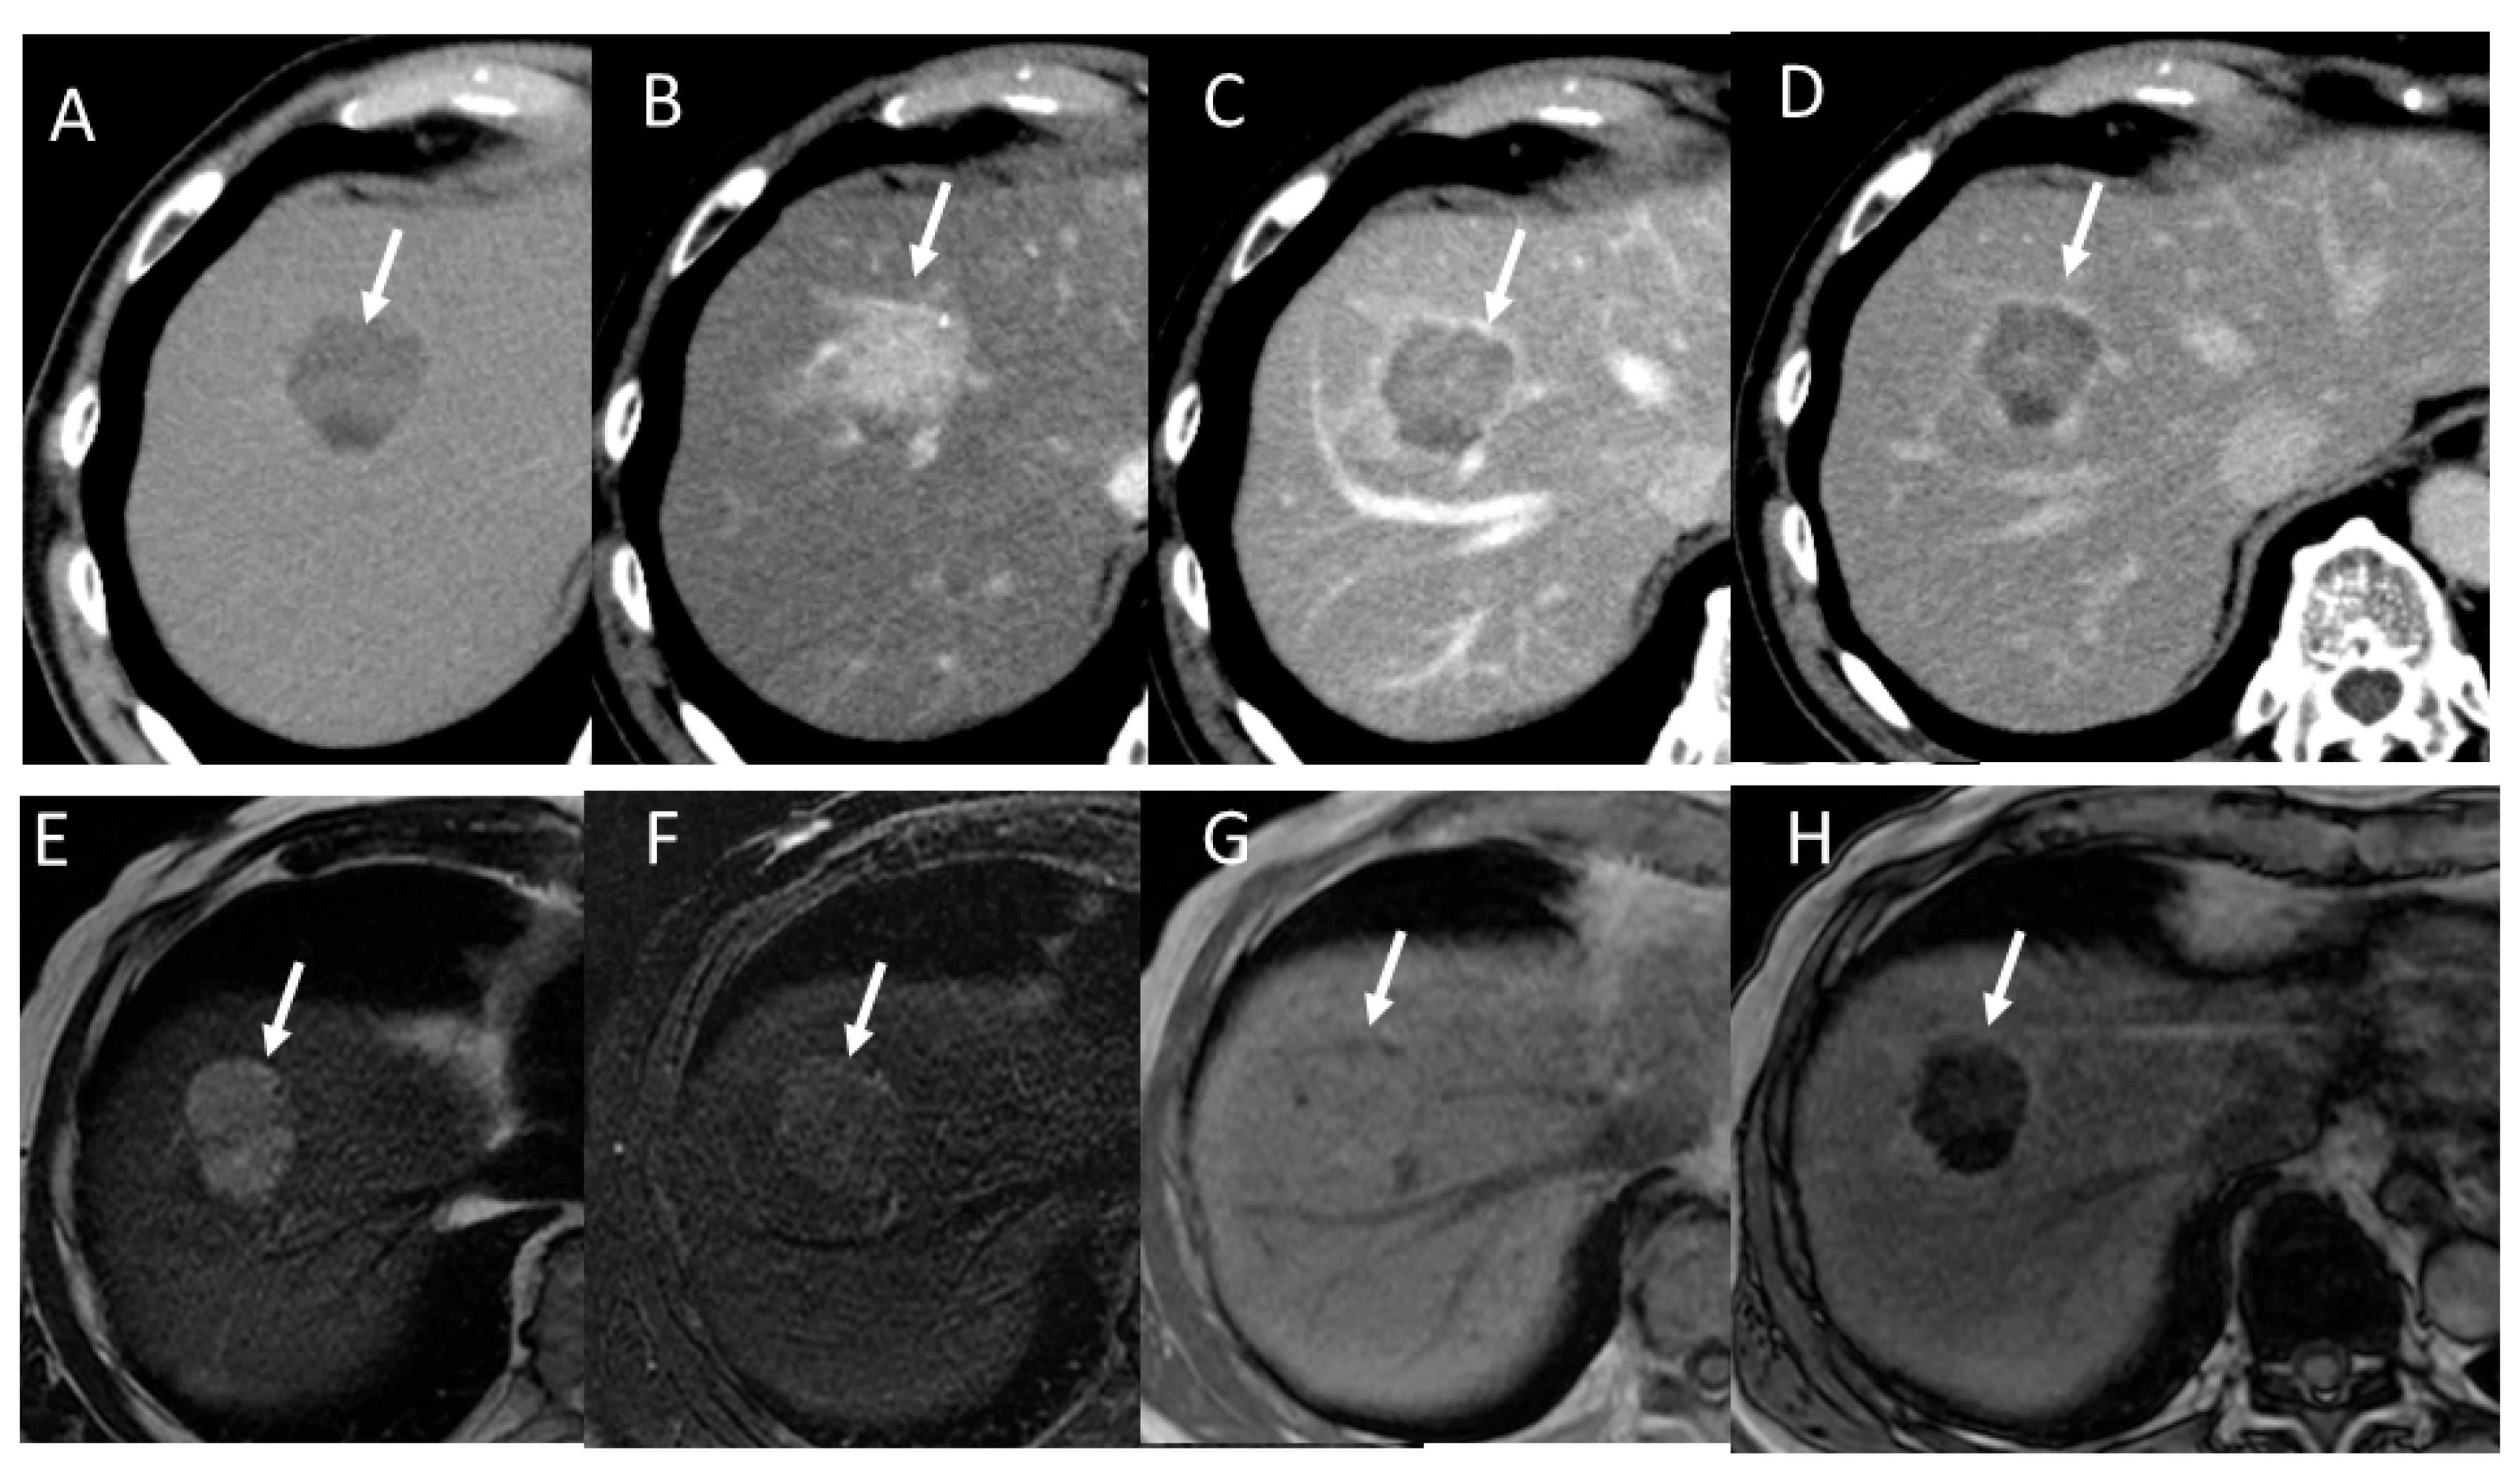

2.1. HCC Imaging on CT

2.2. HCC Imaging on MRI

4.1. Hepatocellular Carcinoma (HCC)

4.2. Early Hepatocellular Carcinoma (Early-HCC)

4.3. Well-Differentiated Hepatocellular Carcinoma (Well-HCC)

4.4. Moderately Differentiated Hepatocellular Carcinoma (Moderately HCC)

4.5. Poorly Differentiated Hepatocellular Carcinoma (Poorly HCC)